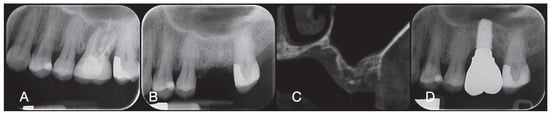

2.1. Socket Preservation Procedure

2.2. Post-Surgical Instructions and Prosthetic Phase After Socket Preservation

2.3. Biopsy Retrieval